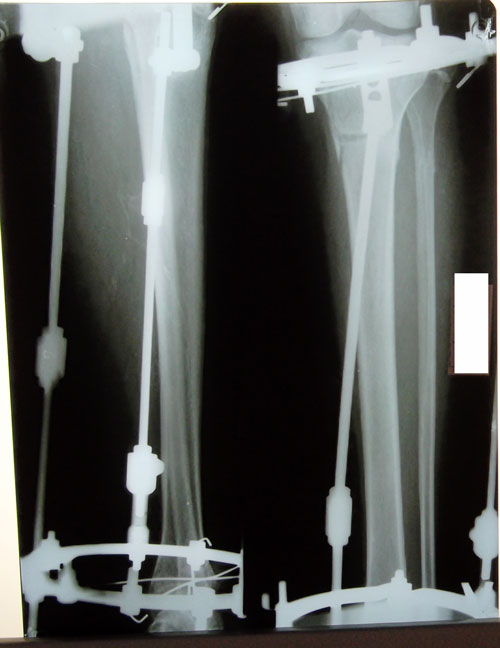

Рентген в 65 дней!

Сращение идёт отлично! В 3 месяца ждём рентген контроль и на снятие аппаратов!

P.S. девочки, всегда Вас прошу делать рентген с коленным суставом! http://klinika-onipko.kz/forums/viewtop ... 05d3a77291